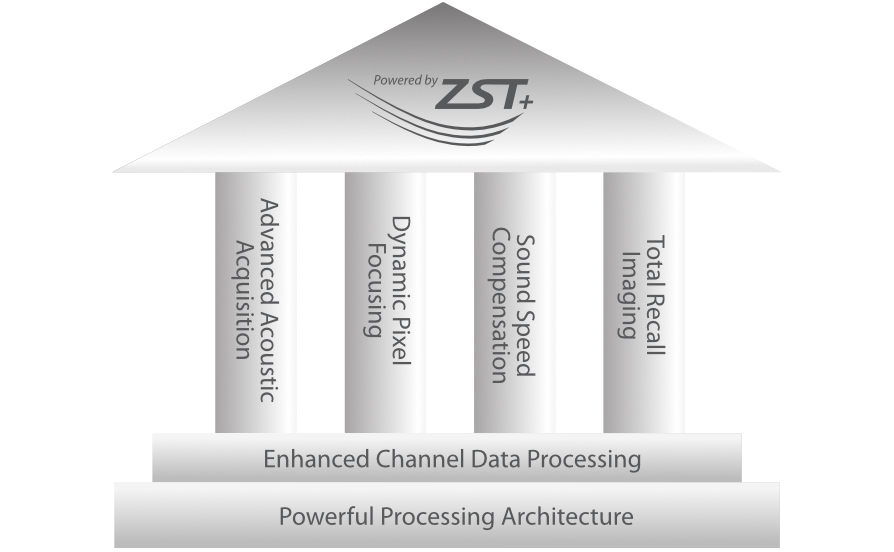

ZST +? ???? ?? ???? ???

ZST+ ???? ???? ??? ???? ??? ?????. ??? ????? ??? ? ???? ?? ??? ?? ????? ?????. ?? ???, ?? ???, ?? ??? ?? ?? ?? ??? ??? ???? ???? ??? ?? ??? ?? ???? ?? ??? ?? ??? ?????.